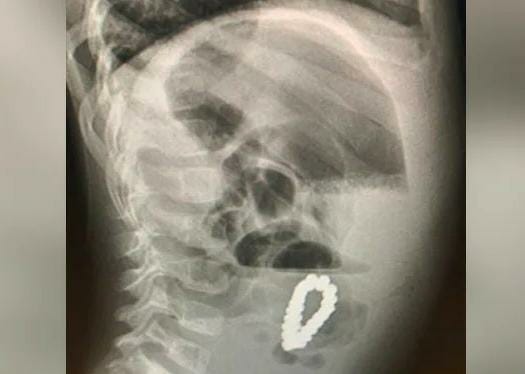

एका 4 वर्षीय मुलाच्या पोटात चक्क मॅग्नेटिक ब्रेसलेट सापडलं. एक्स-रे पाहून डॉक्टरही हैराण झाले आहेत.

मुलाचा एक्स-रे काढला तेव्हा सगळेच चक्रावून गेले. मुलाने नकळत मॅग्नेटिक ब्रेसलेट गिळल्याचे सांगण्यात येत आहे. काही दिवस सर्व काही सामान्य होते, पण नंतर मुलाला पोटात तीव्र वेदना होऊ लागल्या. पालकांना या प्रकरणाची माहिती नव्हती. त्याला घेऊन हॉस्पिटलमध्ये पोहोचताच एक्स-रे पाहून त्यांना मोठा धक्काच बसला.

दोन दिवसांनंतर, लक्षणे पूर्वीसारखीच होती, त्यामुळे काय चूक आहे हे शोधण्यासाठी डॉक्टरांनी अल्ट्रासाऊंड करण्याचा निर्णय घेतला, तेव्हा असे दिसून आले की मुलाच्या पोटात मॅग्नेटिक ब्रेसलेट आहे, ज्यामुळे मुलाला त्रास होत आहे. याच दरम्यान, डॉक्टरांनी इमर्जन्सी लॅपरोटॉमी आणि त्यानंतर उपचार करून 18 चुंबकीय मण्यांनी बनवलेले ब्रेसलेट बाहेर काढलं. एका हिंदी वेबसाईटने याबाबतचे वृत्त दिले आहे.